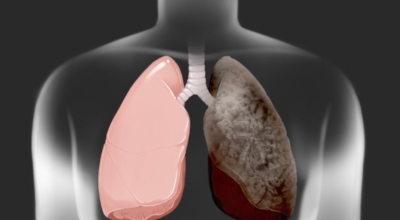

폐암의 공통 위험요소로 손꼽히는 이유가 되는 것으로 흡연이 있답니다. 흡연자는 비흡연자에 견주어 십몇 배는 더 폐암 발병확률이 높다고 하며 어느정도 기간 동안 흡연했는지에 따라 폐암 발생확률은 더더욱 더 높아져요. 흡연자라고 해도 금연을 하게 되면 폐암 발병확률이 가파르게 내려간다고 하니 폐암이 걱정되신다면 가장 먼저 금연은 필수입니다. 간접흡연 외에도 공사장과 같은 곳에서 미세먼지나 석면, 비소, 라돈, 카드뮴 등 신체에 옳지 않은 성분에 노출되는 환경적 요인으로 폐암이 발병할 수 있다고 하며 유전적 요인으로도 폐암이 발병할 수 있다고 하죠. 가족 중 폐암을 앓았던 분들이 있다면 그렇지 않은 분들에 비교해 2배 가량 더 폐암에 걸릴 확률이 높다고 하는데요 이렇듯 폐암은 나도 모르는 새에 발병할 수 있으므로 자신의 신체 컨디션를 수시로 체크하여 폐암을 초기에 발견하는 것이 현명해요.

폐암은 3기 이상인 말기에 발견되는 경우가 대개라 예전에는 폐암 판정을 받으면 곧 사망이라고 하는 말까지 있답니다. 하지만 요즘엔 의료기술이 발달하여 폐암 5년 생존율은 70%가 넘고 있답니다. 무엇보다 주기적인 건강검진으로 인해서 폐암을 조기에 발견한 경우가 많아서라고 볼 수 있어요. 세세히 살펴보면 인산화효소 변이 폐암 환자의 경우 5년, 상피세포 성장인자 수용체 변이 폐암 환자의 경우 1년~3년의 생존율을 보인다고 해요. 하지만 요즘도 폐암을 3~4기에서 확진 받는 경우가 많아요.